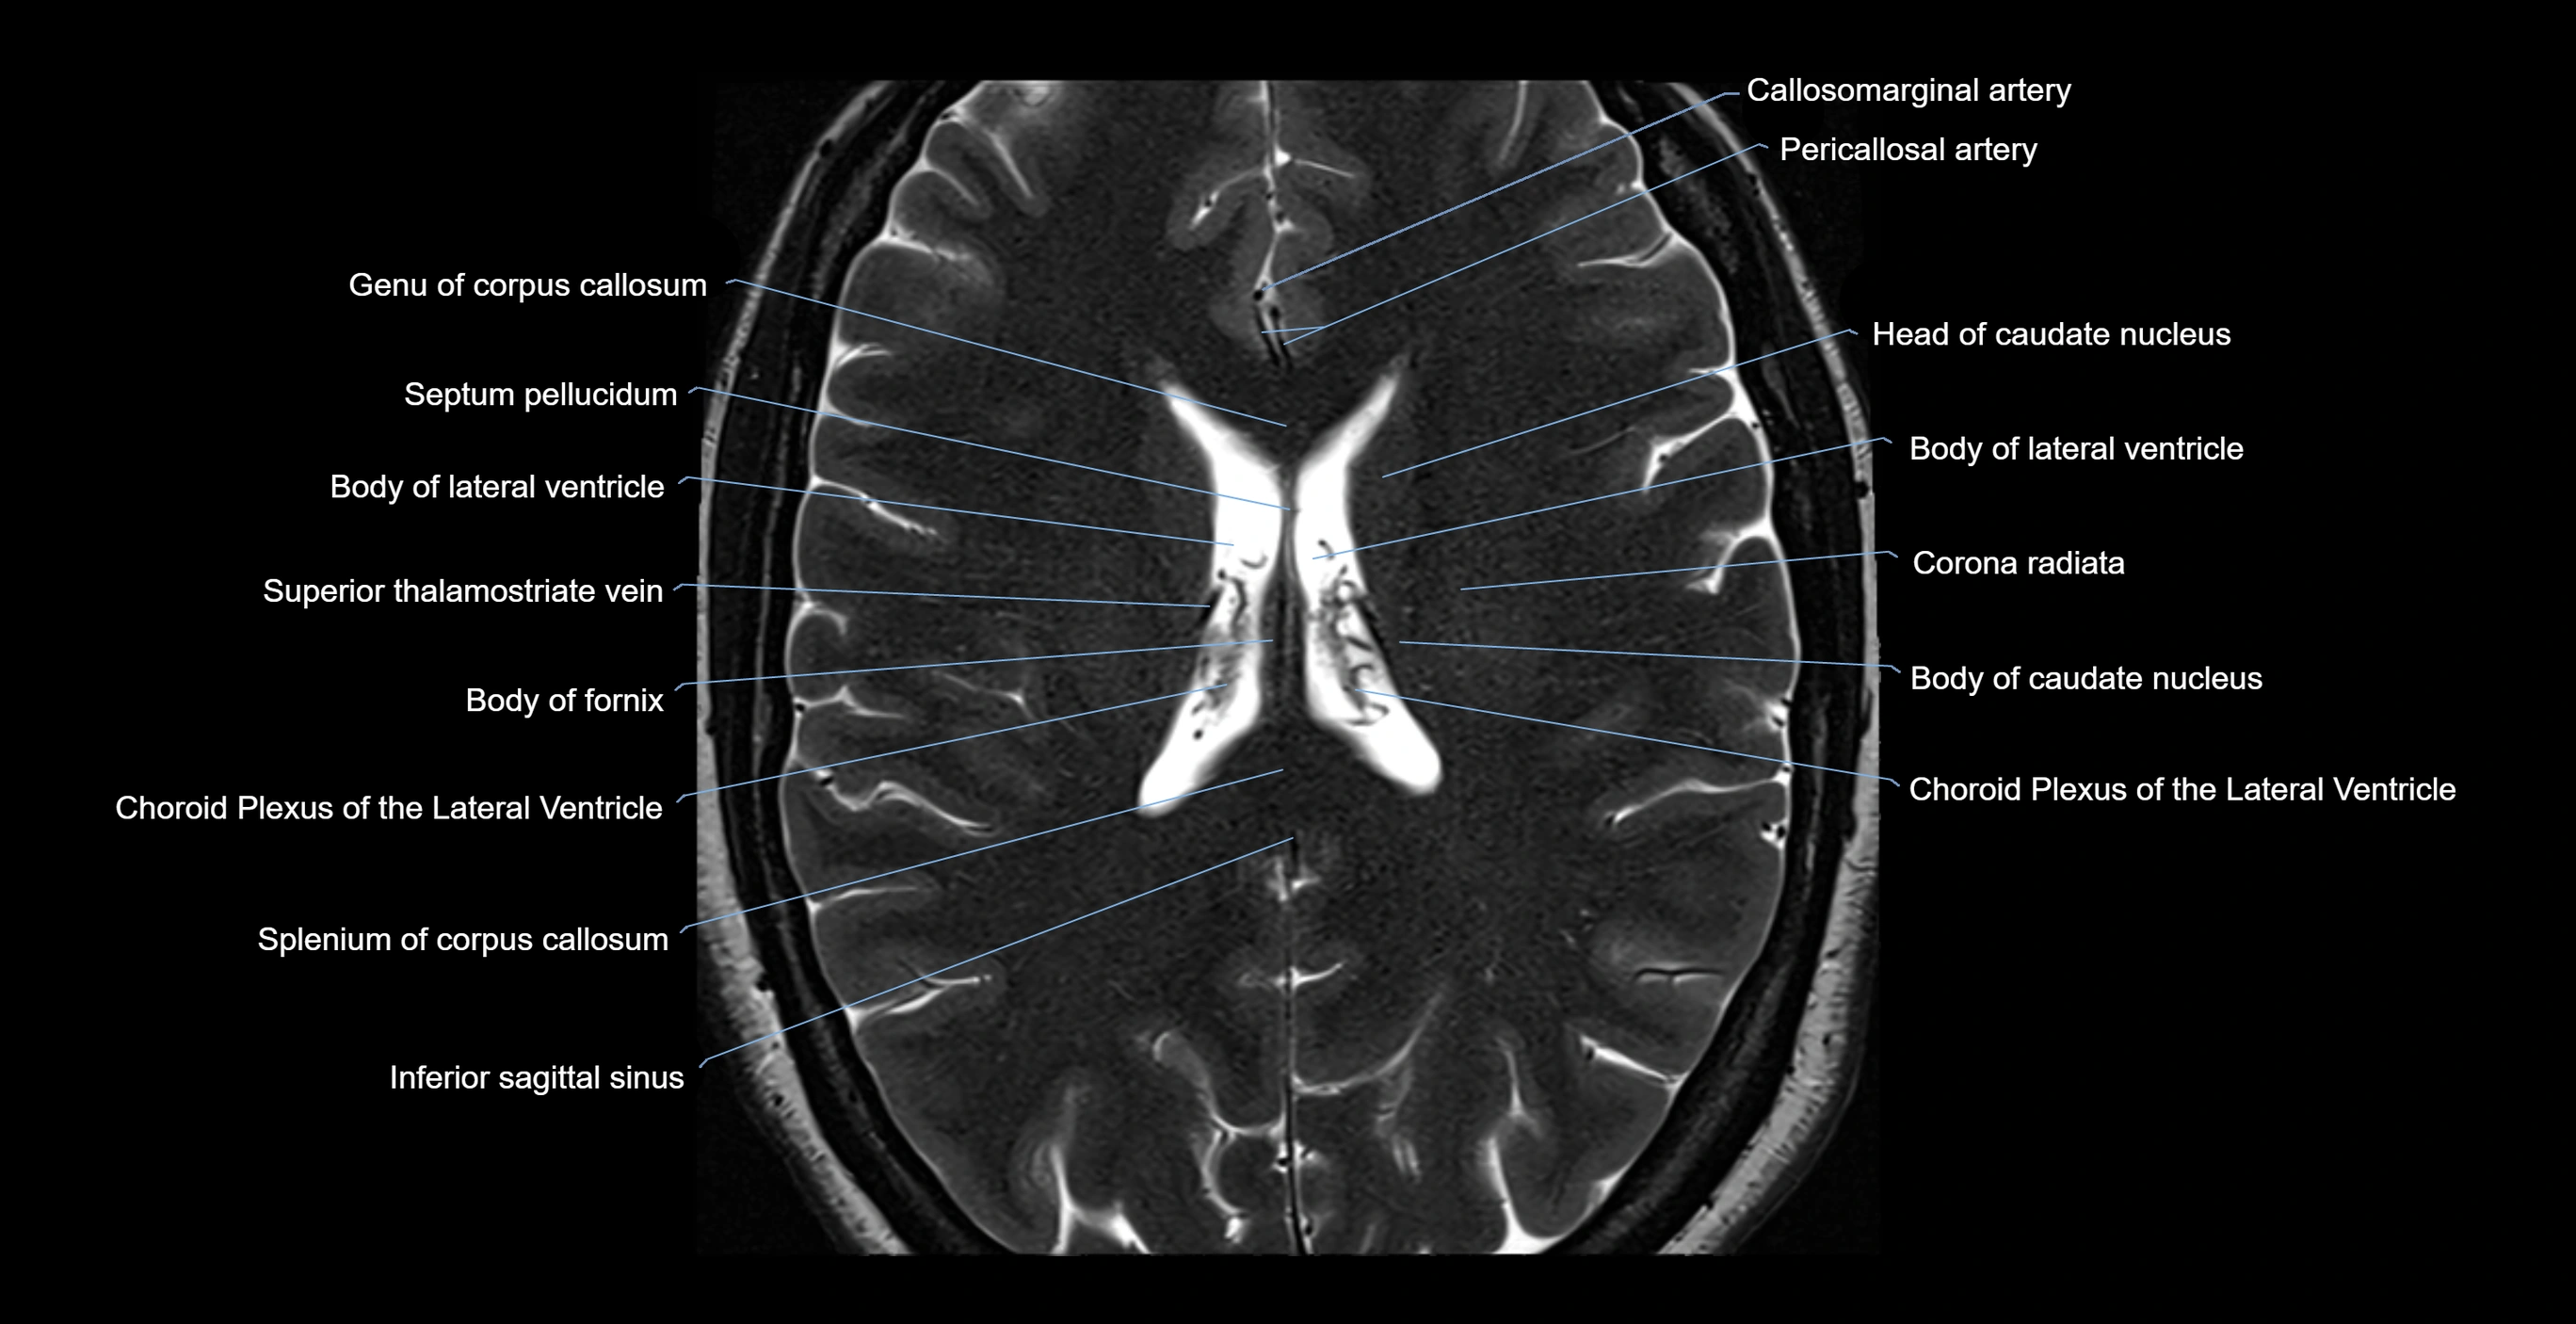

- Body of lateral ventricle

- Callosomarginal artery

- Choroid plexus of the lateral ventricle

- Corona radiata

- Genu of corpus callosum

- Head of caudate nucleus

- Inferior sagittal sinus

- Septum pellucidum

- Splenium of corpus callosum

- Superior thalamostriate vein

- Body of fornix